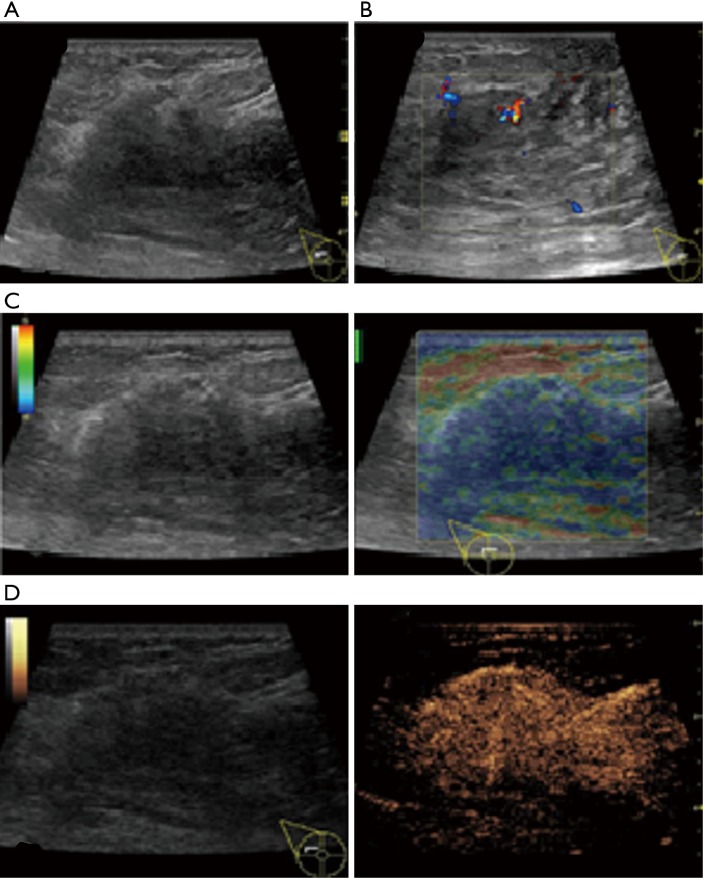

In this study, CEUS of LABC showed high enhancement, and its internal and peripheral blood vessels showed “solar sign” (Figure 1). Relevant studies showed (25) that angiogenic factors could stimulate the breast tissue to produce new blood vessels that extend into the tumor in malignant tumors. And then it would form a network of blood vessels that changed with the growth and necrosis of the tumor. Due to the anisotropy of malignant tumor growth, its internal vascular path was messy, twisted and variable. The characteristic of “solar sign” was often seen as an important indicator for the diagnosis of benign and malignant tumors (23,25). In this study, the tumors of invasive ductal carcinoma all presented as “fast in and slow out”. Analysis suggested that there might be abundant arterial regeneration in the tumor. They were rapidly enhanced. Related studies showed that malignant tumors were composed of abnormal blood vessels with increased tortuosity. It tended to increase flow resistance. At the same time, hypoxia and acidosis decreased red blood cell fluidity. They could also lead to venous insufficiency, poor reflux, and thrombosis, which leaded to form a slow withdrawal (27-29). Some study revealed that breast cancer presented as “fast in and fast out”. It might be because of the formation of arteriovenous fistula inside the tumor. However, Wan et al. [2012] (25) showed that the enhancement mode could also be “fast in and slow out” in benign tumors. It might be related to the blood supply characteristics of the breast tumor. So the mode of enhancement cannot be used as a distinguishing feature of benign and malignant breast tumors. In addition, in this study, 11 lesions (11/40, 27.5%) had no, equal or low enhancement areas, including 5 lesions (5/40, 12.5%) had no continuous enhancement areas. In 3 of the 5 lesions, the internal cystic area was found in conventional ultrasound, but the area of no enhancement in CEUS was significantly larger than that in conventional ultrasound. In 2 lesions, no cystic area was found in conventional ultrasound, but CEUS showed non-liquefaction necrosis area without enhancement (Figure 2). In addition, for non-mass breast cancer, it was difficult to be presented in conventional ultrasound. CEUS could show relatively clear boundaries. In particular, CEUS could clearly show the area of lesions and internal vascular conditions, assisting in diagnosis and guiding the area of puncture biopsy (Figures 3,4). Therefore, CEUS was more likely to detect muscle or skin infiltration than conventional ultrasound, providing a reference for accurate clinical T staging of LABC.

Figure 3.

The features of conventional ultrasound, SE and CEUS (non-mass type) of locally advanced invasive ductal carcinoma in 1 case. Female, 34 years old, right breast had mass for 2 months. (A) Conventional ultrasonography showed the disturbance echo in external superior quadrant of right breast external superior quadrant, no specific boundary was observed; (B) multiple striped blood flow signals was seen in CDFI, some of which formed a net. The blood flow rating was grade 3; (C) SE clearly showed the overall area and boundary of lesion. It was 4 points; (D) CEUS showed high enhancement with clear boundaries. CEUS, contrast-enhanced ultrasonography; CDFI, color Doppler flow imaging; SE, strain elastography.